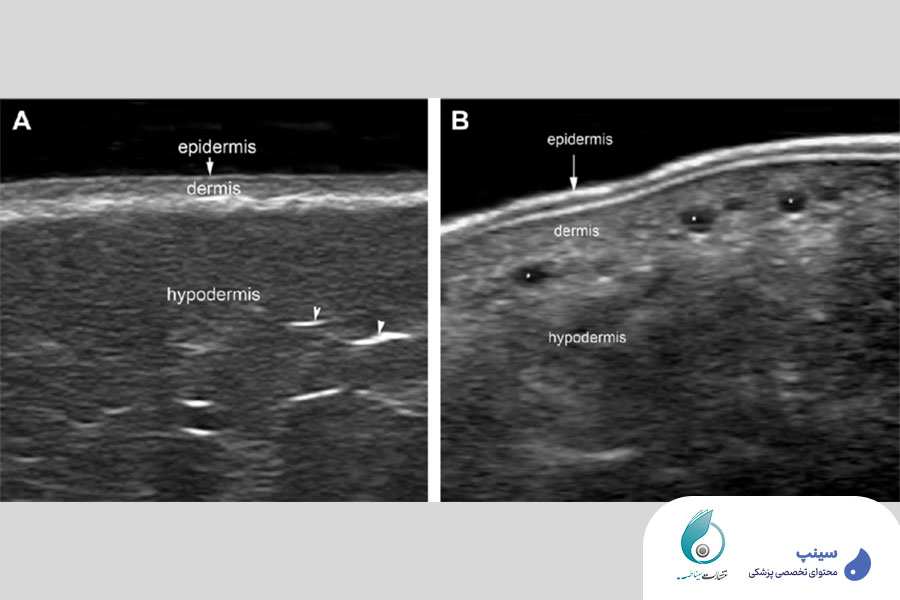

- آناتومی نرمال پوست و صورت

تمامی مباحث مرتبط با آناتومی نرمال پوست و صورت و ضایعات شایع پوستی با استفاده از سونوگرافی به شما آموزش داده خواهد شد. بدین ترتیب، شما به عنوان شرکت کننده این دوره، یاد خواهید گرفت که چگونه با دقت بالا انواع Fat pad های صورت را بررسی نمایید. همچنین نحوه تشخیص دقیق و سریع خونرسانی و عصب دهی صورت را به وسیله سونوگرافی به طور مفصل و با بیانی شیوا و ساده فرا خواهید گرفت.

نمای سونوگرافیک ضایعات شایع پوستی